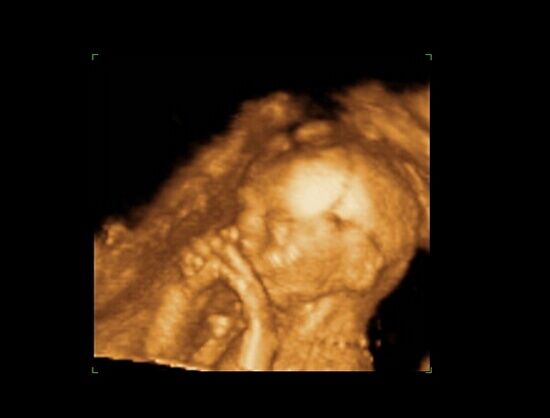

Huhh, hát annyira jó élmény volt, most tök boldog vagyok! Nagyon örülök, hogy mégis elmentem mégegyszer, mert sokat vacilláltam ám. A 4D Genesis egyszerűen szuper, mindenkinek nagyon nagyon tudom ajánlani, ezen belül is engem a Lengyel Györgyné Márti fogadott. Szuper ez a nő, akkora átéléssel és profizmussal csinálta az egész vizsgálatot! Mindent részletesen megnézett, megmutatott, elmagyarázott, nem sajnálta az időt. A felvétel gyönyörű lett, az egész baby nagyon szépen látszik, végig fent volt és mocorgott, hihetetlen aranyos volt, és nagyon szép!

Bemutatott párszor, ezek mind meg is vannak örökítve!

Na és a lényeg...jöjjenek a sztárfotók! Bocsi előre, 8 lesz és kicsit nagyok, de nem tudtam választani, azokat a bemutatásokat mind muszáj volt felraknom, tök vicces!